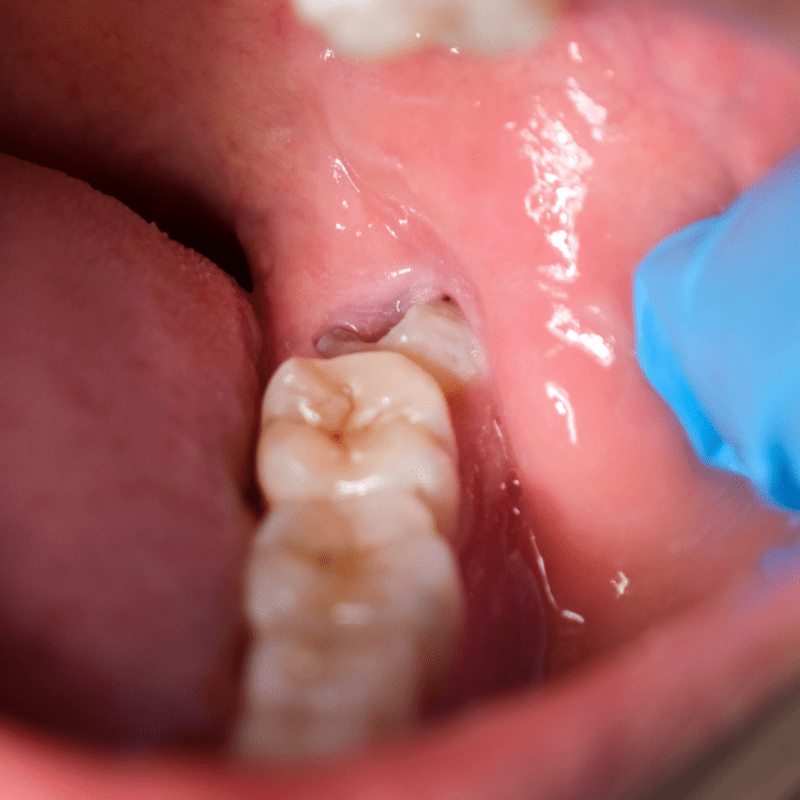

Impacted wisdom teeth, when left untreated, can cause ongoing pain. This is because they are often difficult to clean due to their location and the lack of extra space in your mouth. By having them removed, you may experience fewer and less frequent toothaches.

Wisdom teeth are often difficult to clean because of their location. This can lead to an increased risk of oral infections and even a risk of tooth decay in the adjacent molars surrounding them. By having them removed, you will be able to keep your teeth free from bacteria and other potential hazards.

When wisdom teeth are not removed, bacteria and food particles can build up more easily in hard-to-reach areas, such as around impacted wisdom teeth; this increased buildup can lead to an increased risk of gum disease. Removing them can help reduce your chance of developing gum infection